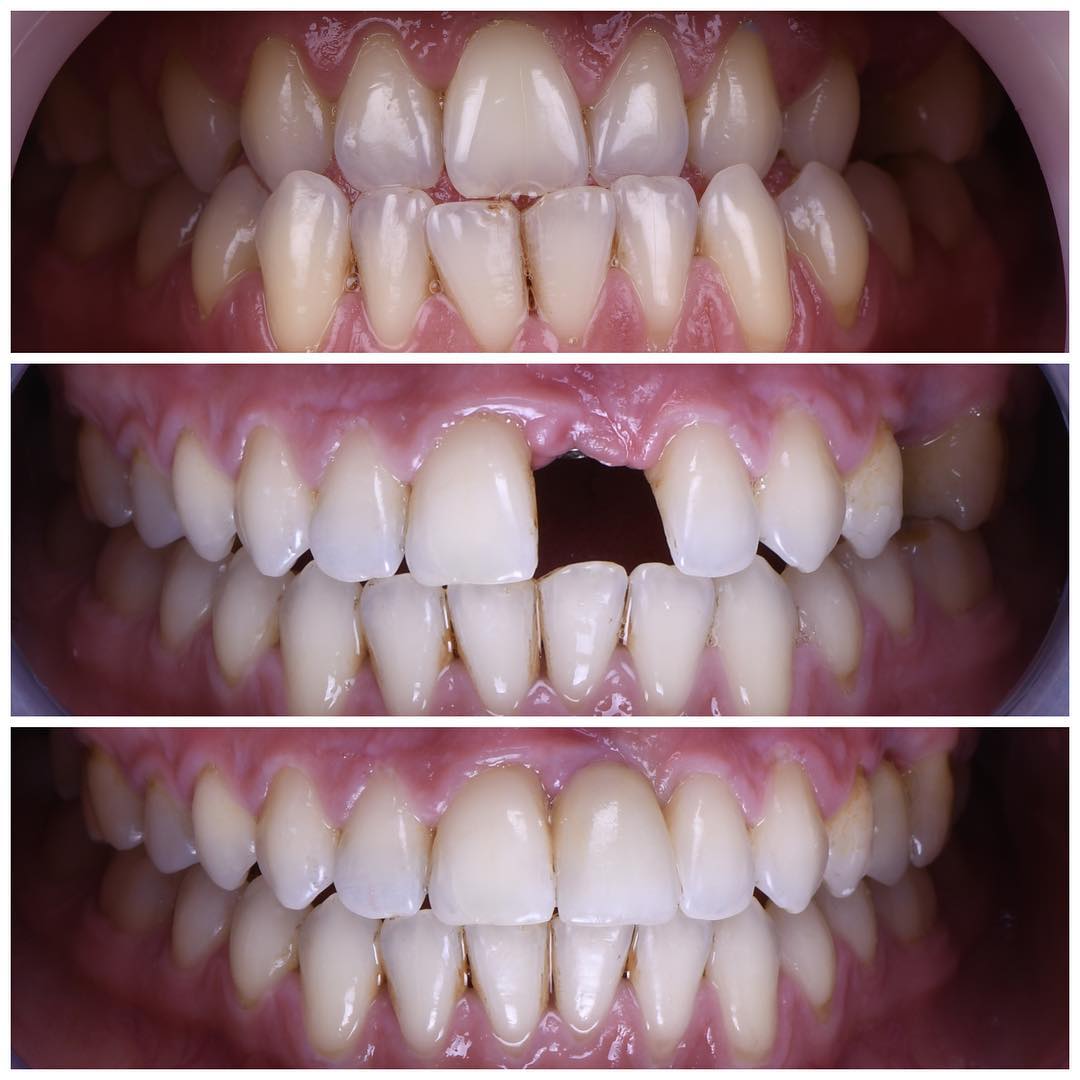

- Kron yani kaplama yöntemi dişlerin ağız içinde görünen kısımlarının düzeltilmesidir.

- Kaplama, şekil ve ağız içi pozisyon bozukluğu olan ve ortodontik tedaviye başvurulmayan dişlerde

- Renkleşmesi ağartıcı ajanlarla tedavi edilemeyen dişlerde